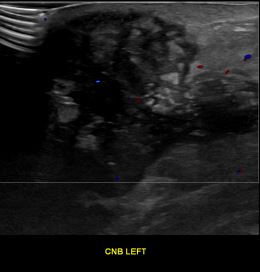

상기환자는 좌측유방 만져지는 멍우리있어  내원하신 40대초반 여성분으로 의심스러운 좌측혹 조직검사 시행해 유방암 진단되었습니다.